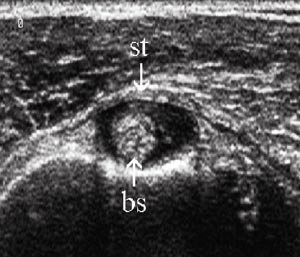

Vurdering av den lange bicepssenen med ultralyd er mer krevende enn vurderingen av rotatorcuffen. Dette skyldes stor interindividuell variabilitet og hyppige artefakter. Sammenlikning og kontroll av funnene med den kontralaterale siden er derfor påkrevd (8). Typiske funn ved tenosynovitt er enten hyper- eller hypotrofi av senen sammenliknet med motsatt side, redusert ekkogenisitet, ekkofattig halo rundt senen og hvelving av sulcustaket over rotatorcuffnivå (e-fig 11) (3, 9).

Subluksasjon og luksasjon av senen skjer vanligvis i medial retning, og er følge av en skade i det stabiliserende kapsulo-ligamentære apparatet i sulcusområdet. Her inngår musculus supraspinatus og subscapularis som viktige elementer, og bicepsseneluksasjon er derfor ofte kombinert med skade i disse delene av rotatorcuffen (e-fig 12) (1) – (3, 8).